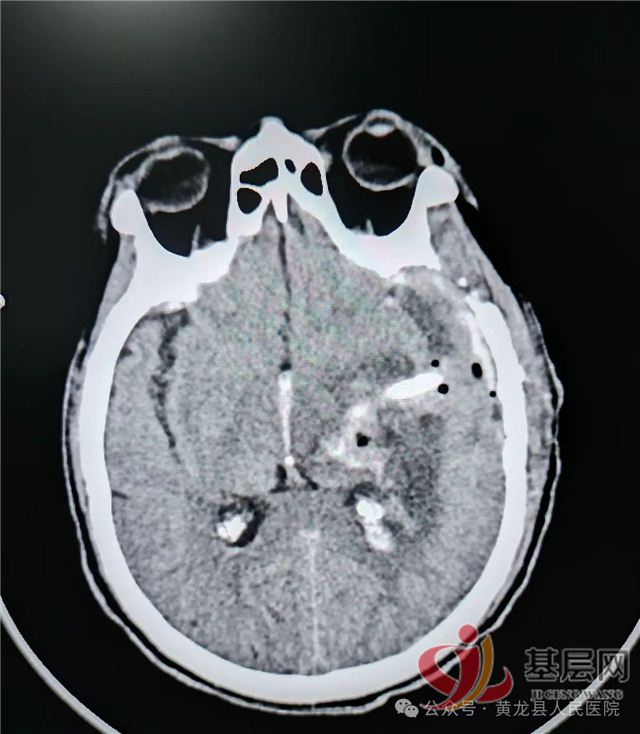

术后第1天复查:颅内血肿基本清除,脑受压减轻